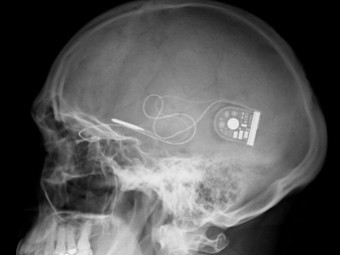

Alpha IMS представляет собой 1500-пиксельный микрочип размером три на три миллиметра, вживленный не в, а под сетчатку, что обеспечивает лучшее оптическое разрешение. Каждому светочувствительному пикселю соответствует фотодиод, анализирующий яркость поступающего в глаз света, усилитель и электрод, передающий сигнал на близлежащие нейронные слои сетчатки и на зрительный нерв, полностью имитируя таким образом работу клеток-фоторецепторов. Яркость и контрастность изображения регулируется самим пациентом с помощью пульта на батарейках, беспроводным образом связывающегося с подкожно вживляемым за ухом усилителем, который, в свою очередь соединен с микрочипом тончайшим кабелем.